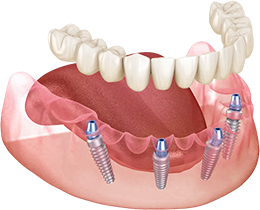

По уникальной методике

БЕЗ отёков и надрезов

Установка

за 1 день